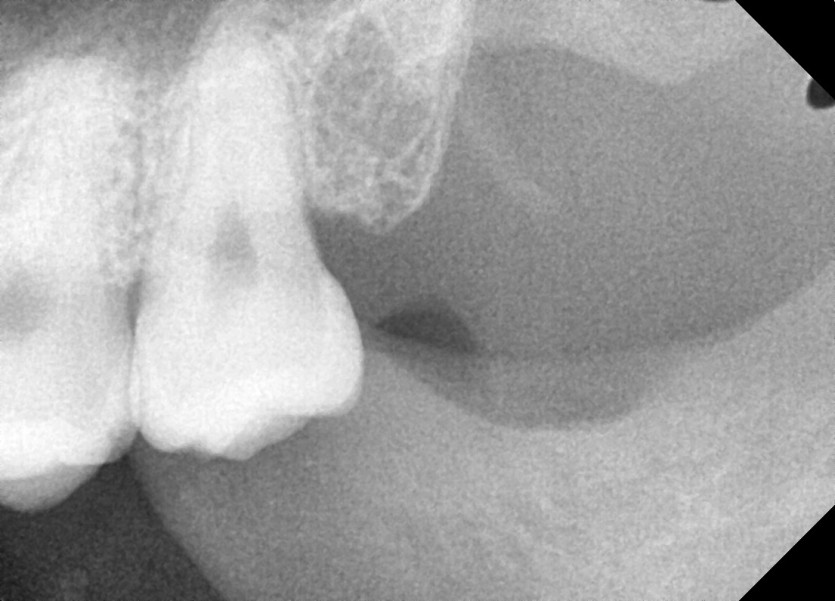

#28, 38 사랑니 발치

구강 외과 전문의가 당일 발치했습니다.